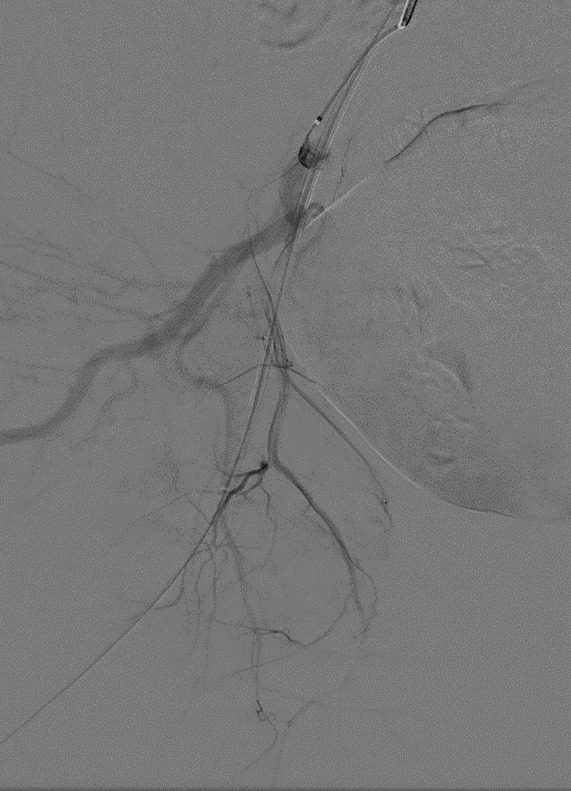

On POD #50 from the hysterectomy, the patient presented to the office with persistent vaginal cuff bleeding, less brisk than prior presentation. There were no sources of bleeding identified on exam. The patient then underwent a CT scan without any evidence of intraabdominal bleeding. Given persistent bleeding without a clearly identifiable source, the decision was made to proceed with bilateral embolization of the anterior divisions of the internal Iliac arteries. The embolization led to resolution of the vaginal cuff bleeding.

This patient’s localized labia minora pain was the result of nontarget labial embolization during bilateral internal Iliac artery embolization. The internal pudendal artery and uterine artery are adjacent to each other, branching off the anterior portion of the internal iliac artery. The internal pudendal artery supplies the labia minora. Most likely, injection of embolic material into the ligated uterine artery resulted in the reflux of particles into the right internal pudendal artery, producing ischemia in the branches supplying the labia.